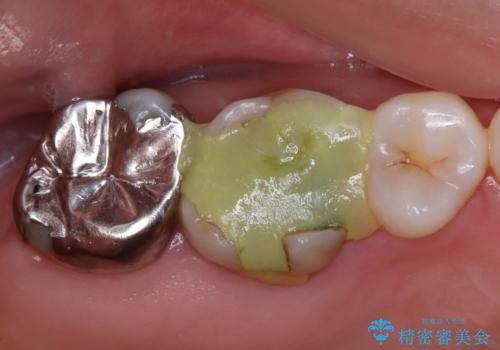

拡大鏡視野下で虫歯の除去を行い、オールセラミッククラウンに適した形に整えました。

型どりはシリコーン印象材にて精密印象をしています。